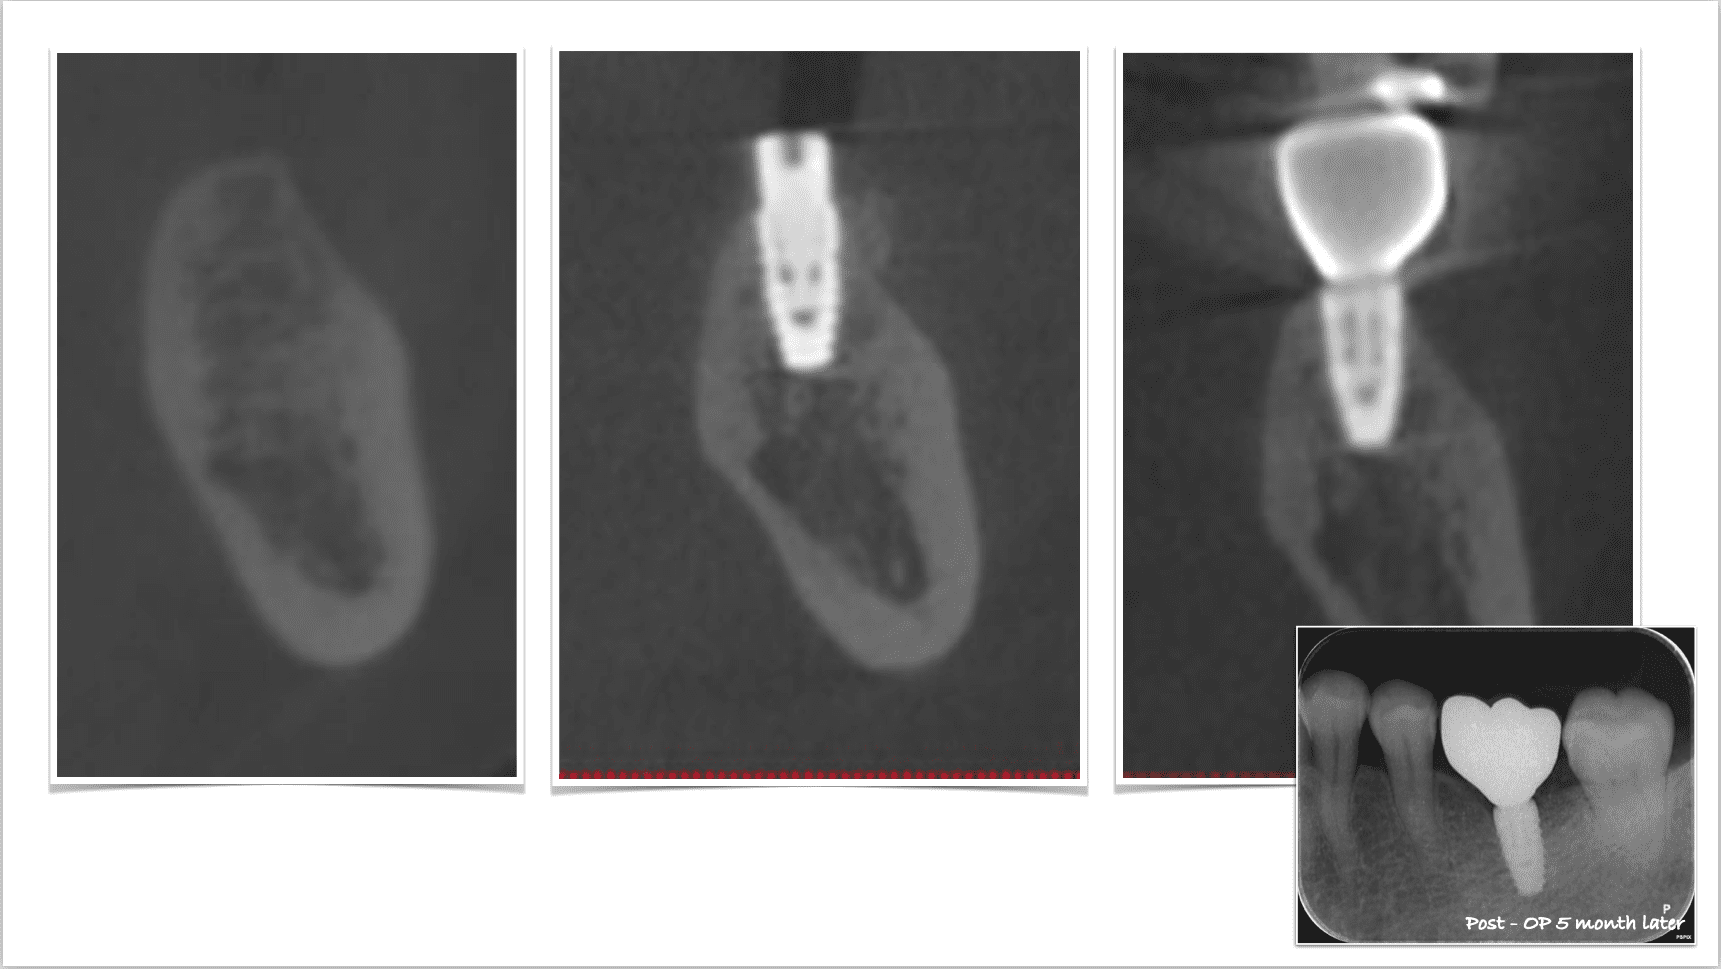

症例紹介29:インプラント治療/前歯_ソケットシール《50代女性》

治療内容:食事中に前歯が破折し、治療を希望し来院。

上顎:折れた歯を見ると、一部被せ物に歯が残っており保存不可能な状態。

上顎:歯には太い土台が入っており、折れて保存不可能な状態

リスク:残っている歯の一部を残してインプラントを入れることによって、歯茎が下がるのを抑えることができます。